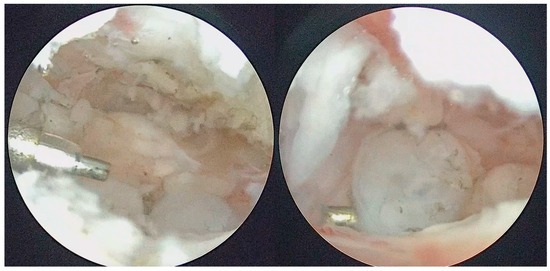

Figure 5.

Arthroscopic removal of LBs and synovial nodules using forceps.

Figure 8.

LB sample sent for histopathological analysis.